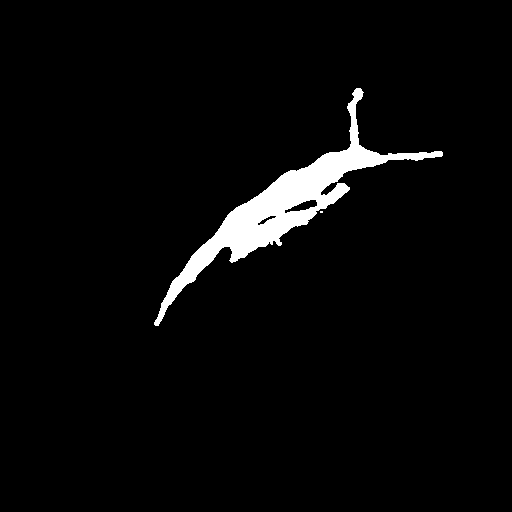

Raw

GT

AURA-net

3.5 Failure Cases

In Figure 3, we illustrate failure cases in dataset . In the first example, AURA-net fails to correctly segment the bottom part of the object. This outcome is unsurprising considering that the raw image exhibits a lower SNR than any of the training data. In the second example, the segmentation mask predicted by AURA-net contains several objects, yielding a poor overlap with the ground truth annotation featuring a single cell. However, the original image reveals the presence of a second, partially cropped non-annotated cell. In this case, part of AURA-net’s “false” detection are actually correct predictions that have been omitted in ground truth annotations.